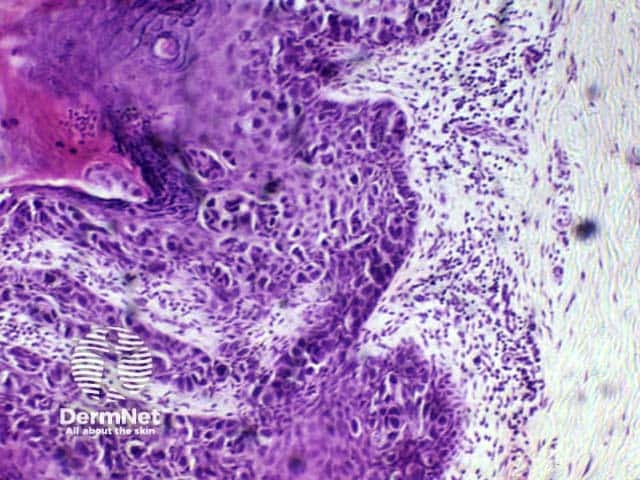

Lesions showing follicular differentiation contain basaloid cells resembling the follicular bulb, adjacent mesenchymal cells resembling the papilla, ‘shadow’ cells and trichilemmal (outer root sheath) cells, i.e. palisading pale cells with a thickened basement membrane.

Benign solitary or multiple follicular tumours include:

Trichoepithelioma

Pilomatricoma

Trichodiscoma